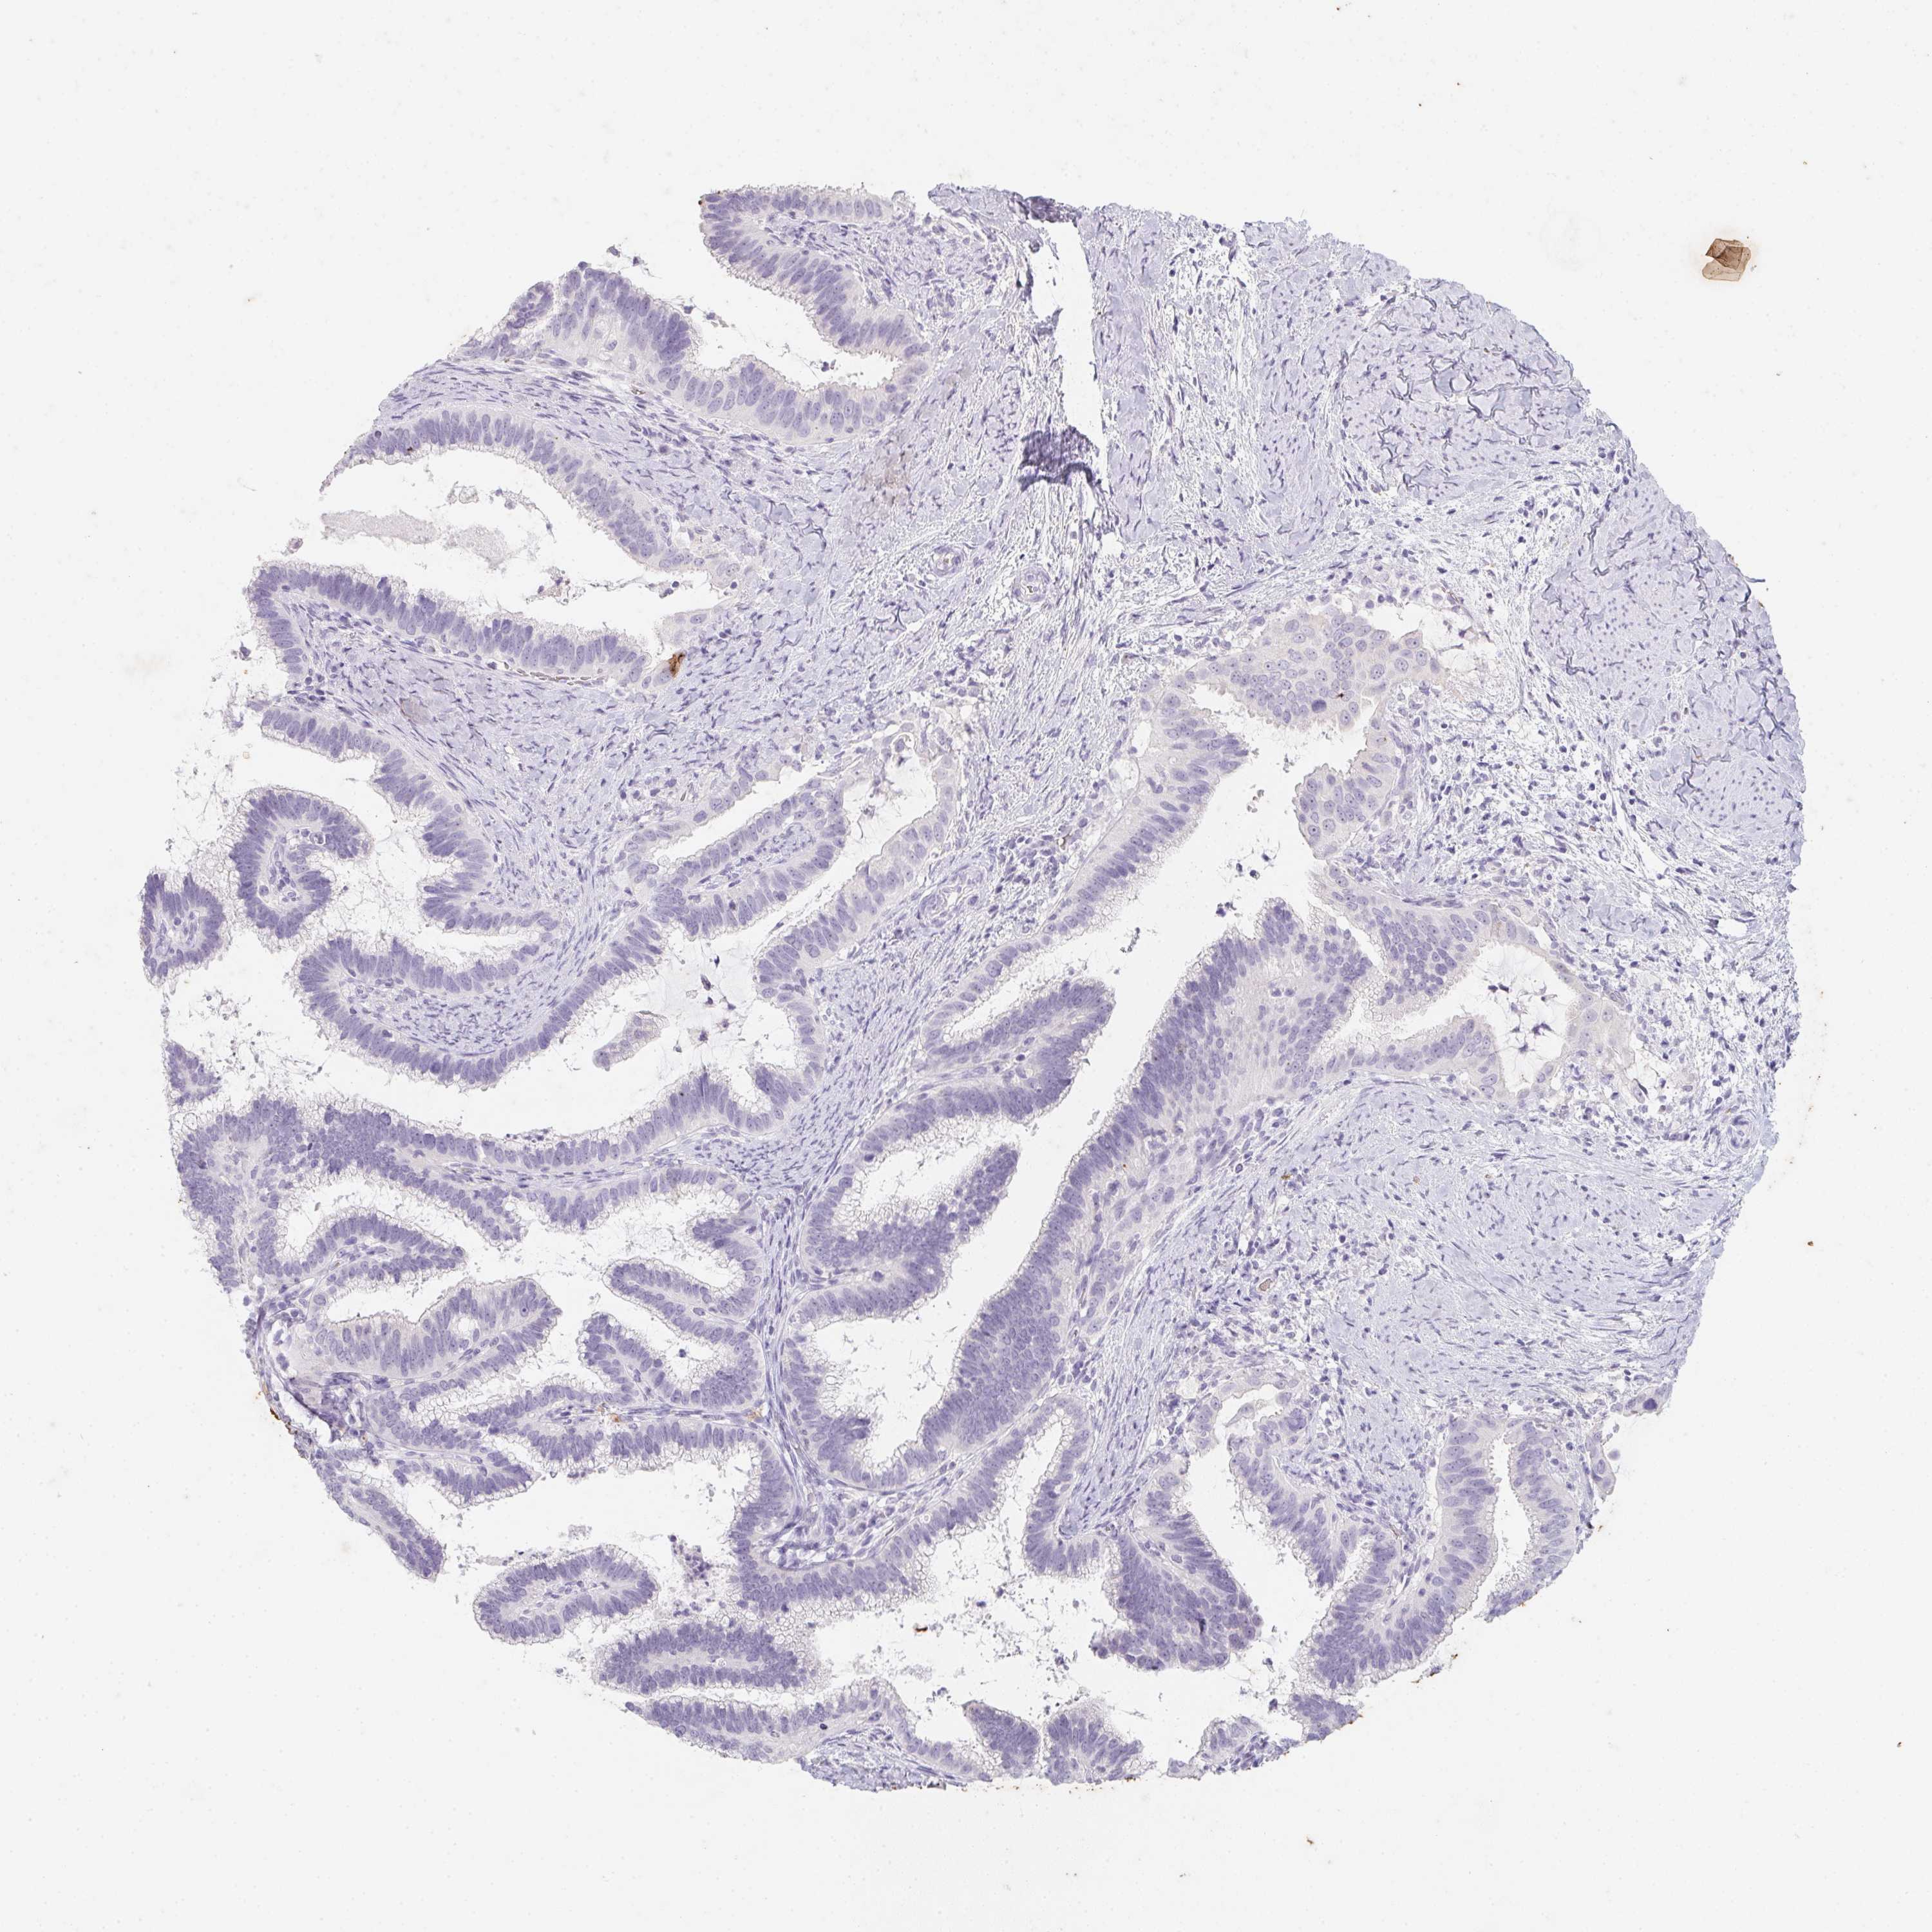

CERVICAL CANCER - Protein expressioni

A mouse-over function shows sample information and annotation data. Click on an image to view it in a full screen mode. Samples can be filtered based on level of antibody staining by selecting one or several of the following categories: high, medium, low and not detected. The assay and annotation is described here.

Note that samples used for immunohistochemistry by the Human Protein Atlas do not correspond to samples in the TCGA dataset.

Antibody stainingi

Antibody staining in the annotated cell types in the current human tissue is reported as not detected, low, medium, or high, based on conventional immunohistochemistry profiling in selected tissues. This score is based on the combination of the staining intensity and fraction of stained cells.

Each image is clickable and will lead to virtual microscopy that enables deeper exploration of all samples and also displays staining intensity scores, fraction scores and subcellular localization as well as patient and tissue information for each sample.

Antibody HPA063967

Staining

High

Medium

Low

Not detected

Intensity

Strong

Moderate

Weak

Negative

Quantity

>75%

75%-25%

<25%

None

Location

Nuclear

Cytoplasmic/membranous

Cytoplasmic/membranous,nuclear

Squamous cell carcinoma, NOS

Adenocarcinoma, NOS